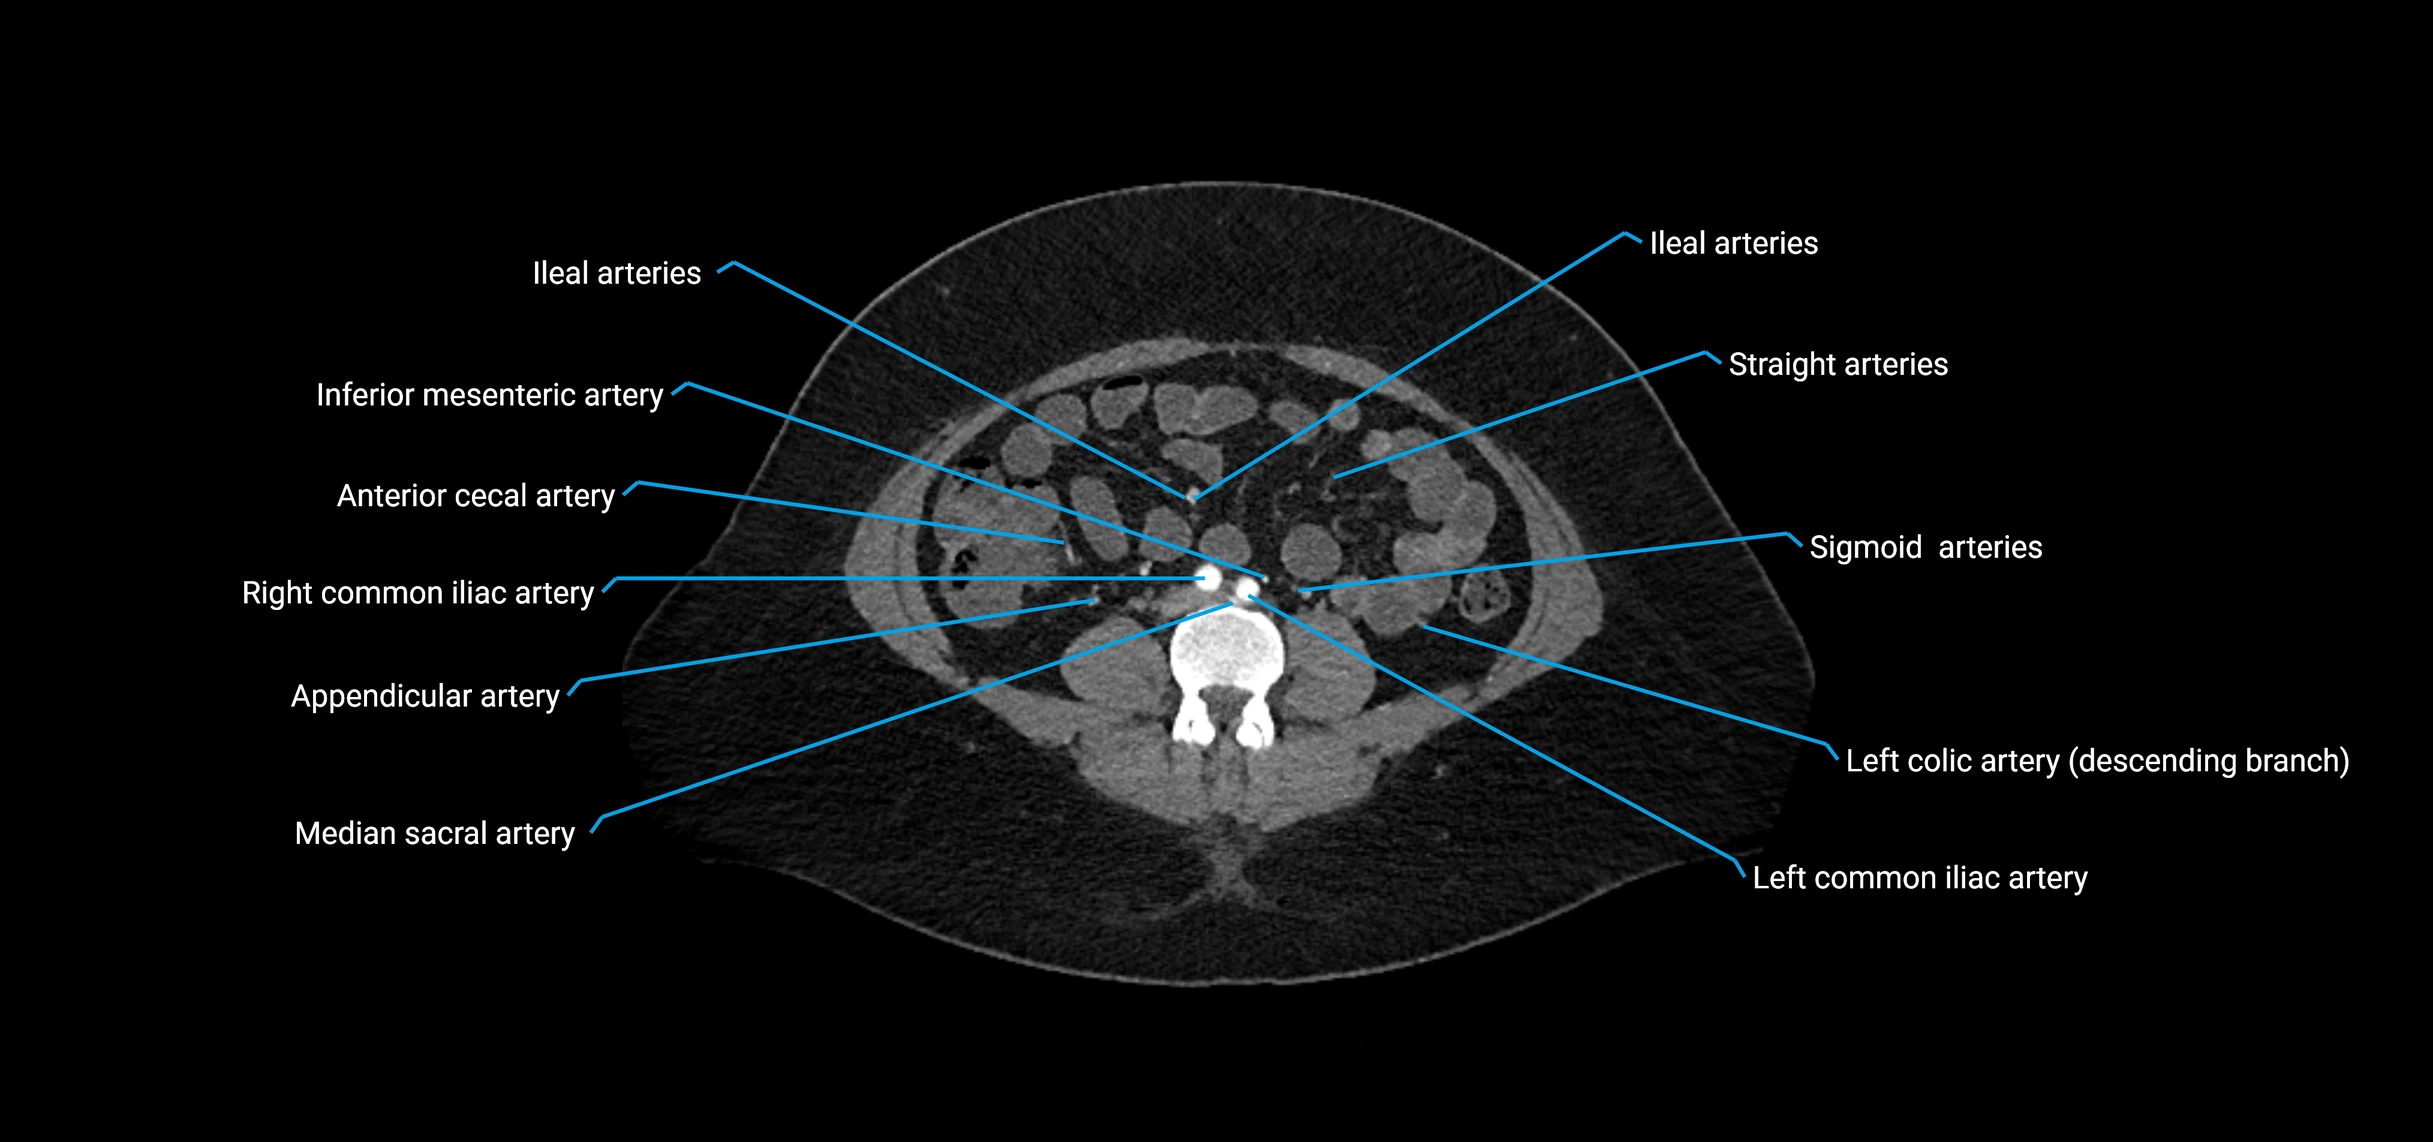

CT Appearance

Non-contrast CT:

• Appears as a tubular soft tissue structure anterior to vertebral bodies

• Calcified atherosclerotic plaques appear as hyperdense foci along the wall

• Useful for screening abdominal aortic aneurysm (AAA) size and mural calcification

Contrast-enhanced CT (CTA):

• Gold standard for abdominal aortic imaging

• Provides excellent detail of lumen, wall, aneurysm, thrombus, and branch vessels

• Multiplanar and 3D reconstructions help in aneurysm measurement, stent graft planning, and dissection evaluation

• Detects acute rupture, traumatic injury, or occlusion with high sensitivity

CT images

image